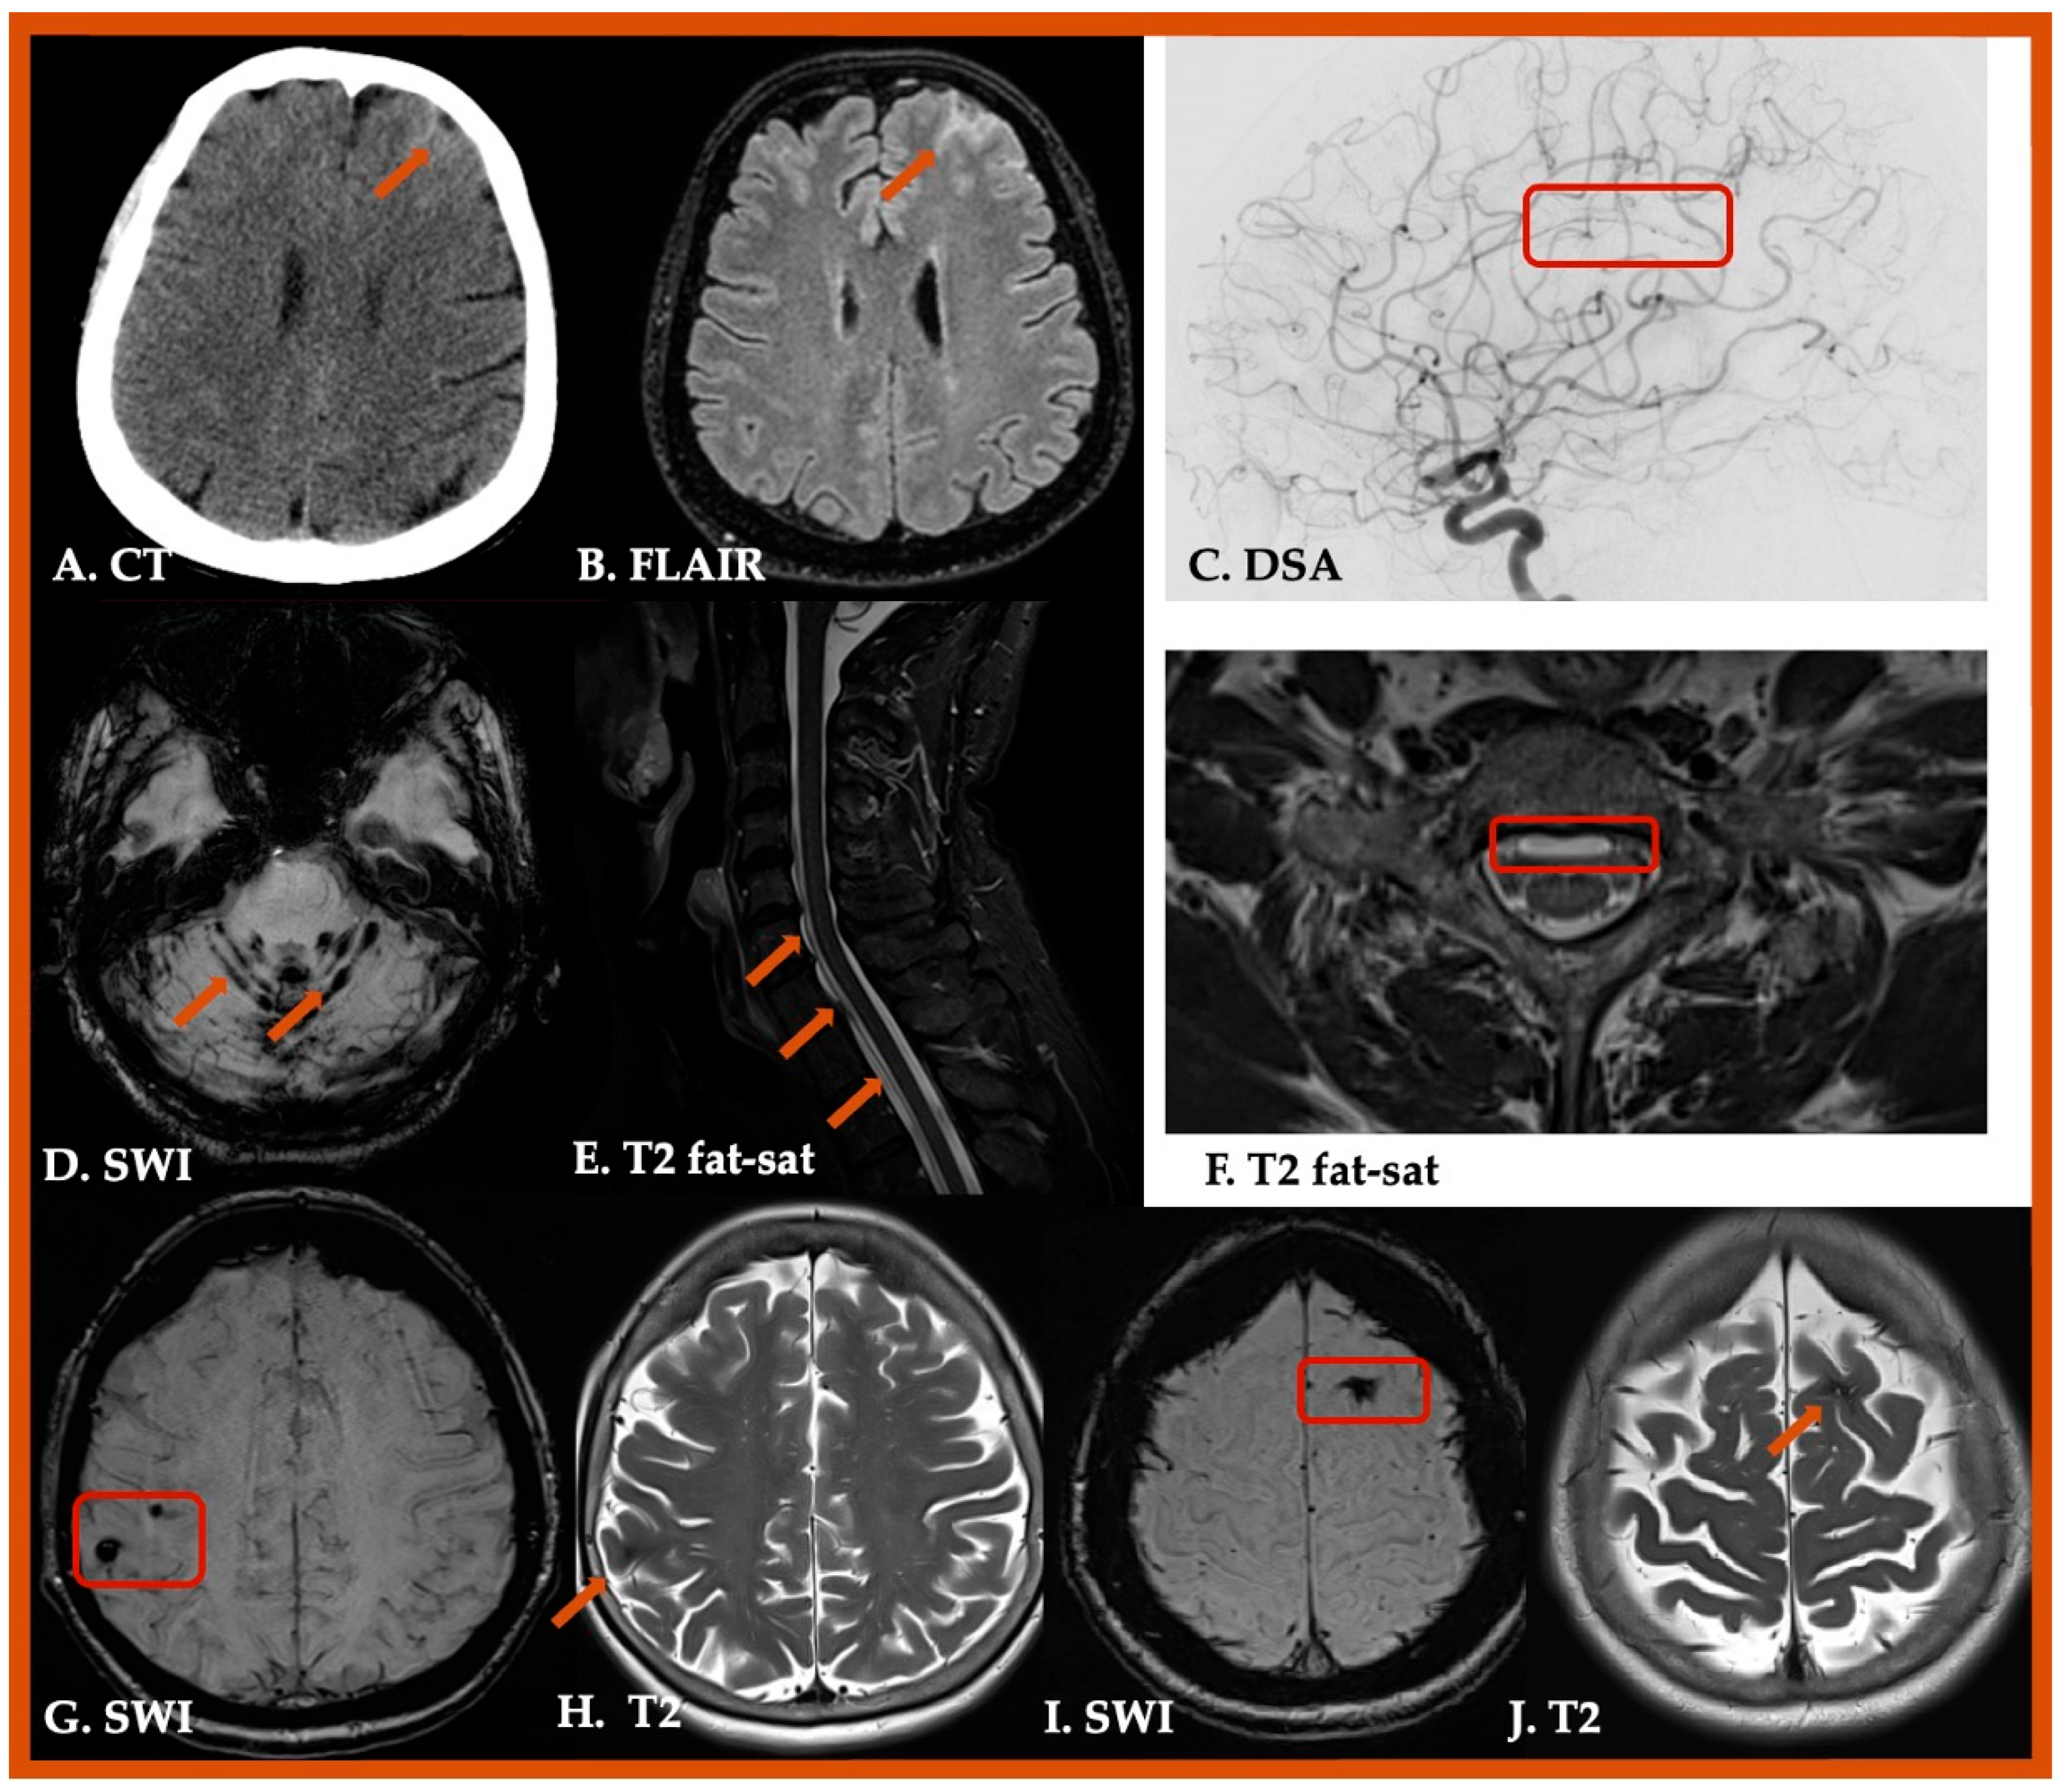

| Conditions Mimicking CAA, CAA-ri, Iatrogenic CAA, and Hereditary CAA | |

|